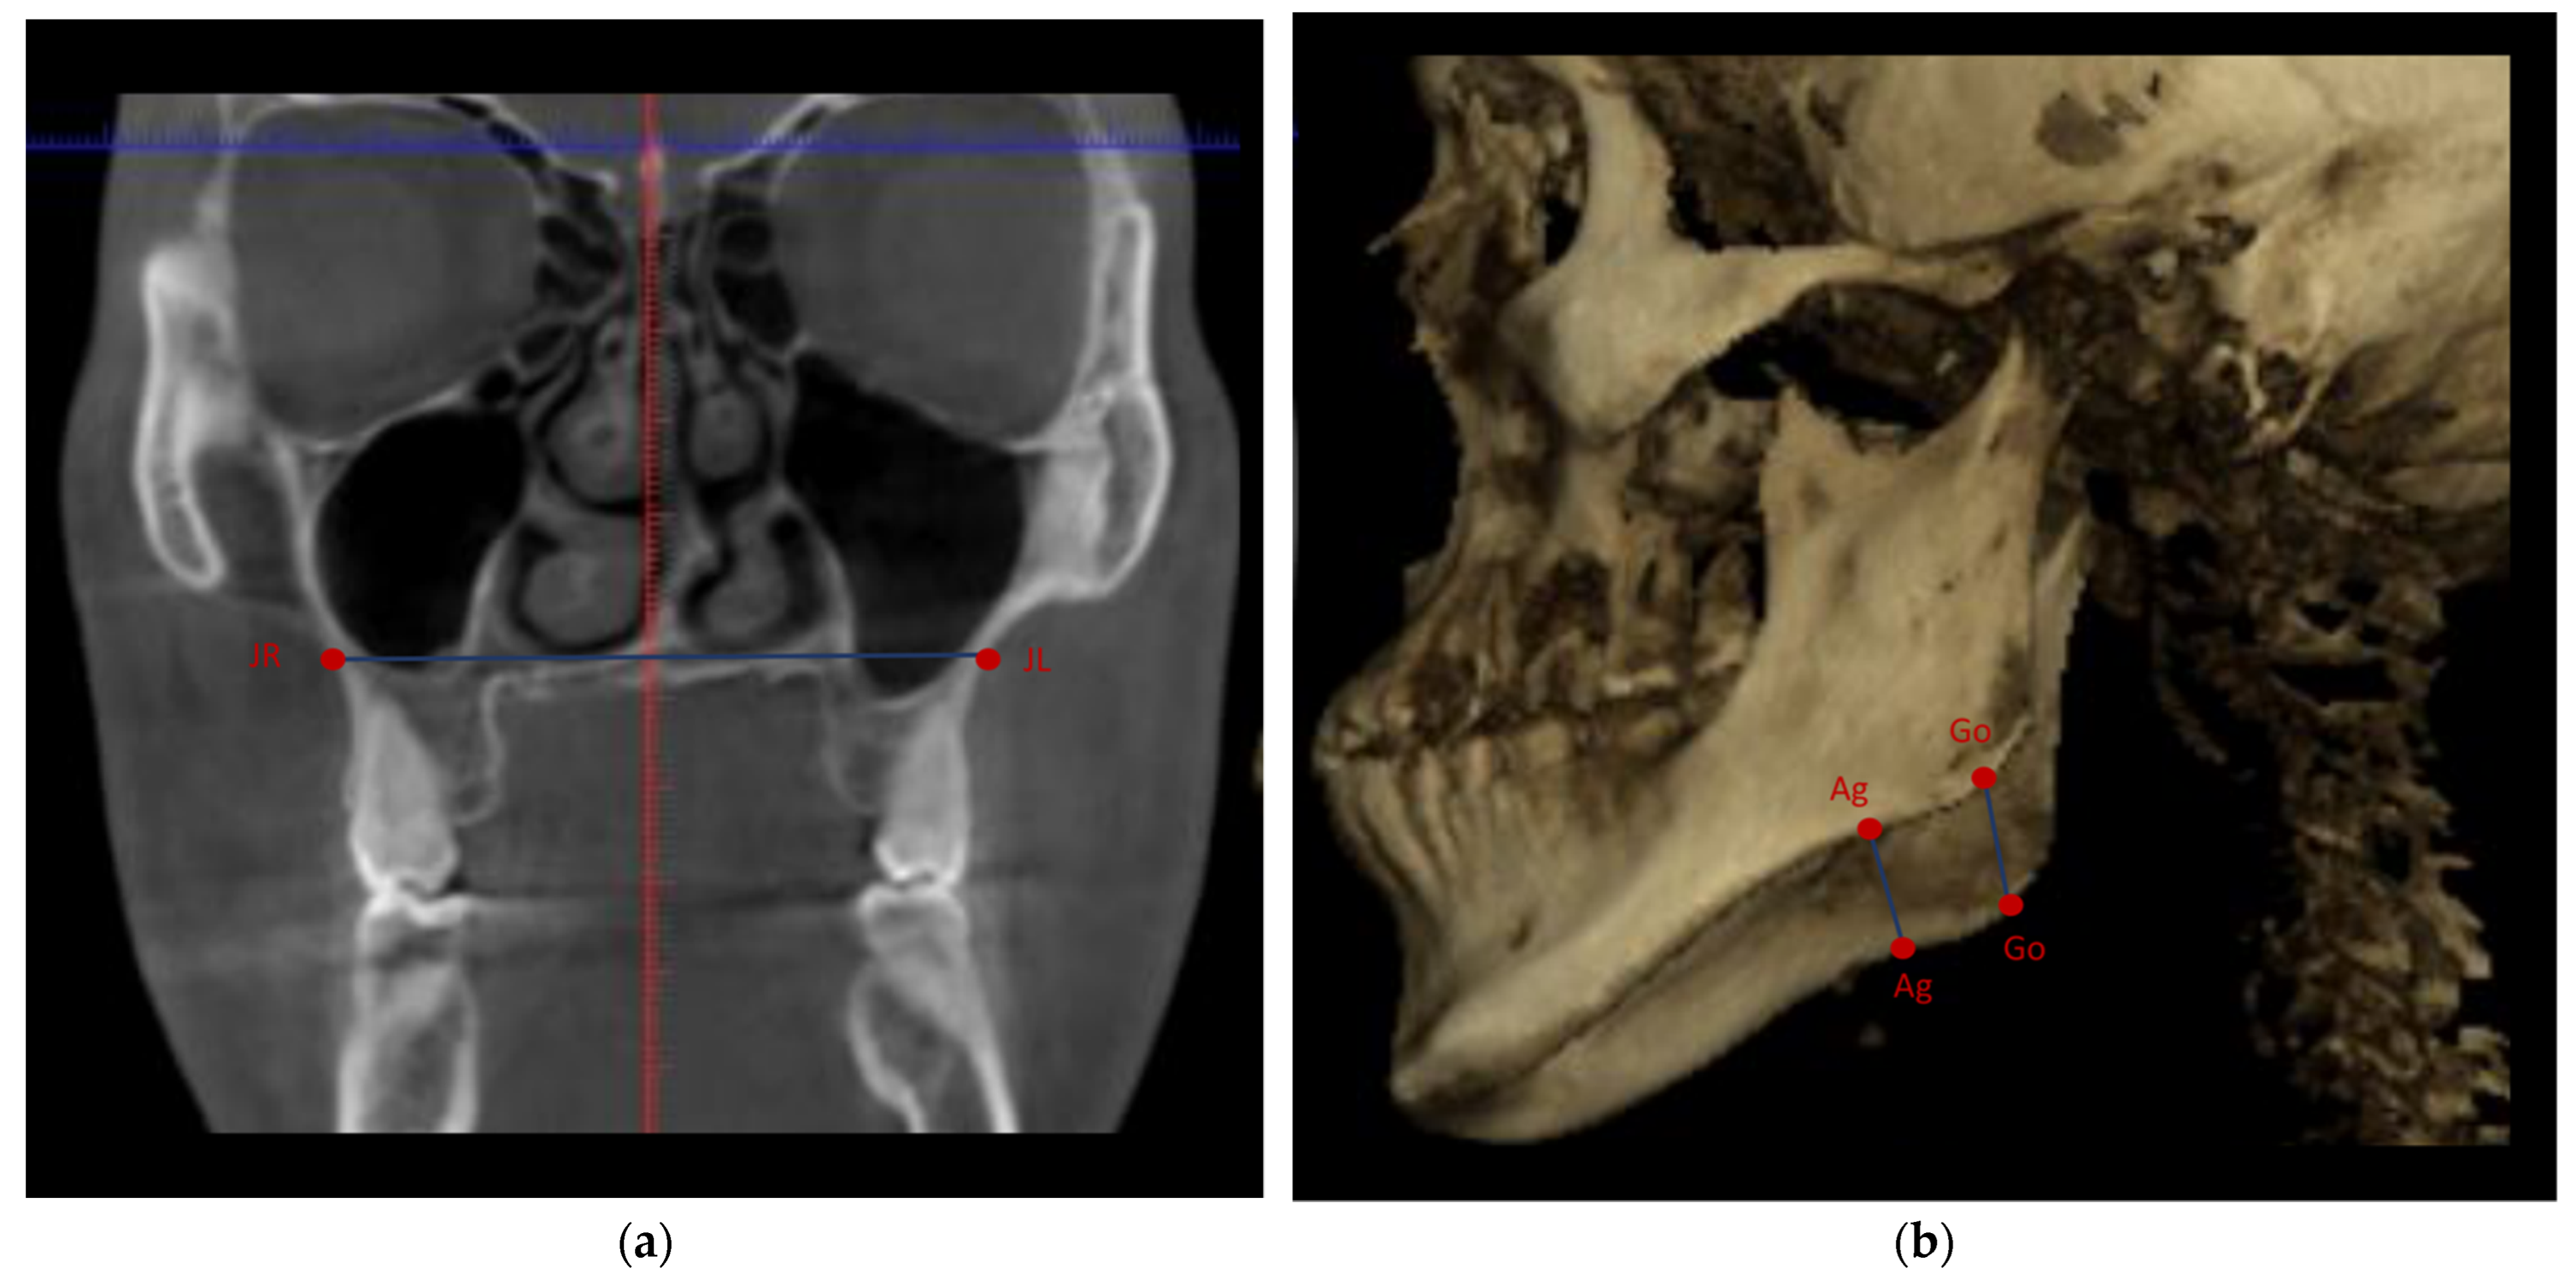

| Landmark | Abbreviation (Unit) | Definition | Sagittal View | Axial View | Coronal View |

|---|---|---|---|---|---|

| Cranial width | Bieuryon width (mm) | Distance between the most lateral points on the cranium in millimeters | Distance between the right inferior-most lateral point of the cranium to the contralateral side | Distance between the right posterior-most lateral point of the cranium to the contralateral side | Distance between the right inferior-most lateral point of the cranium to the contralateral side |

| Maxillary width | JR-JL (mm) | The jugal process is the intersection of maxillary tuberosity outline and zygomatic buttress. Distance between the right jugal process and left jugal process in millimeters | Distance between the inferior-most point of the right jugal process and the inferior-most point of the left jugal process | The point determined on the sagittal and coronal views | Distance between the deepest midpoint of the right jugal process and the deepest midpoint of the left jugal process |

| Gonion right-Gonion left | Go (r)-Go (l) (mm) | Mandibular width in millimeters | Distance between the right inferior- and posterior-most point of the mandibular corpus to the contralateral side | Distance between the right posterior-most point of the mandibular corpus to the contralateral side | Distance between the right inferior-most point of mandibular corpus to the contralateral side |

| Antigonion right-Antigonion left | Ag (r)-Ag (l) (mm) | Mandibular width in millimeters | Distance between the right inferior and posterior of the notch of the lower border of the body of the mandible to the contralateral side | Distance between the right posterior of the notch of the lower border of the body of the mandible to the contralateral side | Distance between the right deepest midpoint of the lower border of the body of the mandible to the contralateral side |